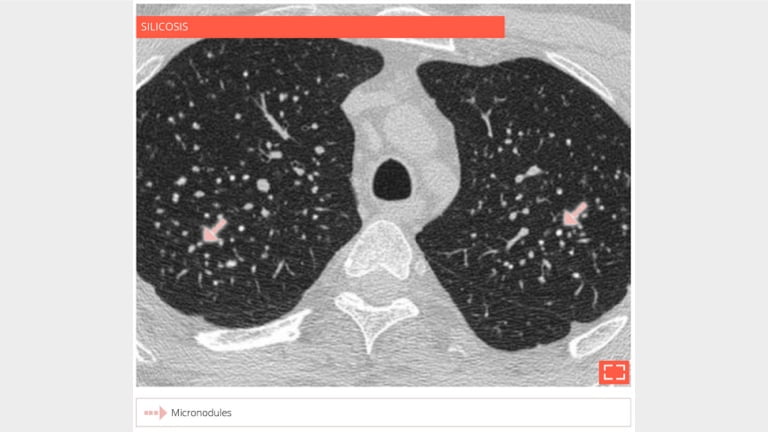

Micronodulation

• Focal rounded opacities < 3 mm presenting the following characteristics:

• Attenuation: ground glass opacity or tissular or even calcified

• Borders: blurry to clear

• The location of micronodulations helps guide the diagnosis:

• within the secondary pulmonary lobule: key to diagnosis

• The CT scans helps categorise diffuse micronodulations based on three types of lobular distribution, thereby significantly reducing the differential diagnosis: